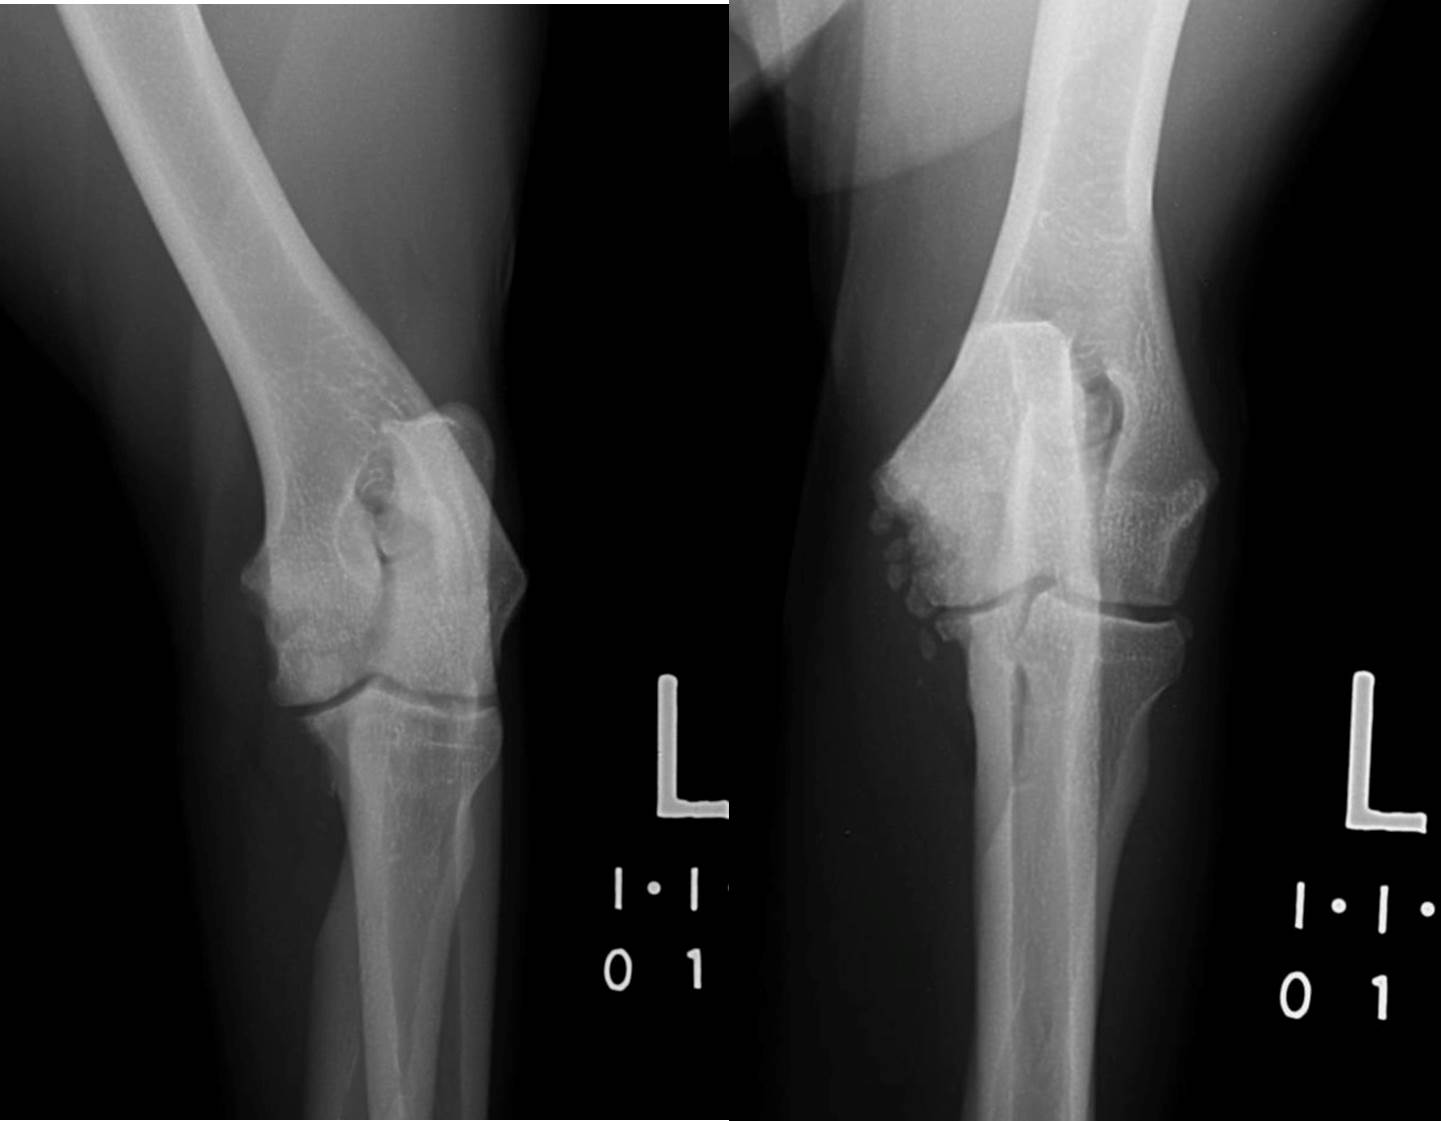

Elbow Dysplasia in Dogs KYON

From www.kyon.ch

Elbow Dysplasia in Dogs KYON Osteomyelitis Dog Xray to describe signalment, clinical signs, serologic test results, treatment, and outcome of dogs with coccidioides osteomyelitis (com) and. osteomyelitis in dogs is a serious condition that requires rapid, intensive treatment. enrofloxacin is used only in dogs, administered at 10 mg/kg, every 12 hours. In addition, wound debridement, lavage, and removal of loose implants. In addition, wound debridement,. Osteomyelitis Dog Xray.